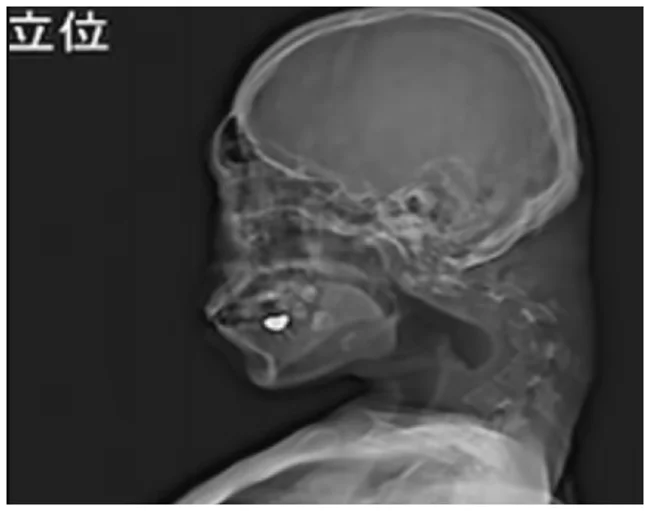

25-летний японец настолько любил играть в игры на телефоне, что практически всё свое время, не поднимая головы, прокачивал свои скилы. В результате продолжительного сидения в позе креветки у него произошла деформация шейного отдела позвоночника.

Парняга потерял возможность поднять голову, не мог нормально есть и прилично сбросил в весе. Когда ситуация уже практически достигла своего апогея, он все же решил обратиться к врачам, те знатно от увиденного удивились.

Сначала медики пытались исправить синдром опущенной головы с помощью воротников — медицинских приспособлений, которые надеваются на шею и поддерживают и стабилизируют голову.

Однако, поскольку пациент жаловался на онемение при ношении устройств, данное лечение было прекращено. Решили проблему сурово, провели парочку операций, удалили лишнее, вкрутили ему в шею ряд винтов и металлических стержней, чтобы исправить осанку.